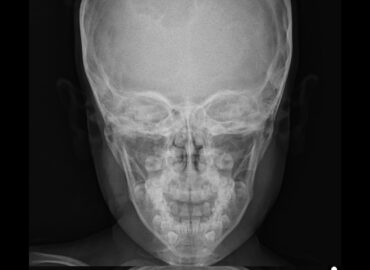

6 años Tumoracion de craneo

Paciente de 71 años de edad, que consulta por cefalea frontal de 1 mes de evolución, asociada a rinorrea, […]